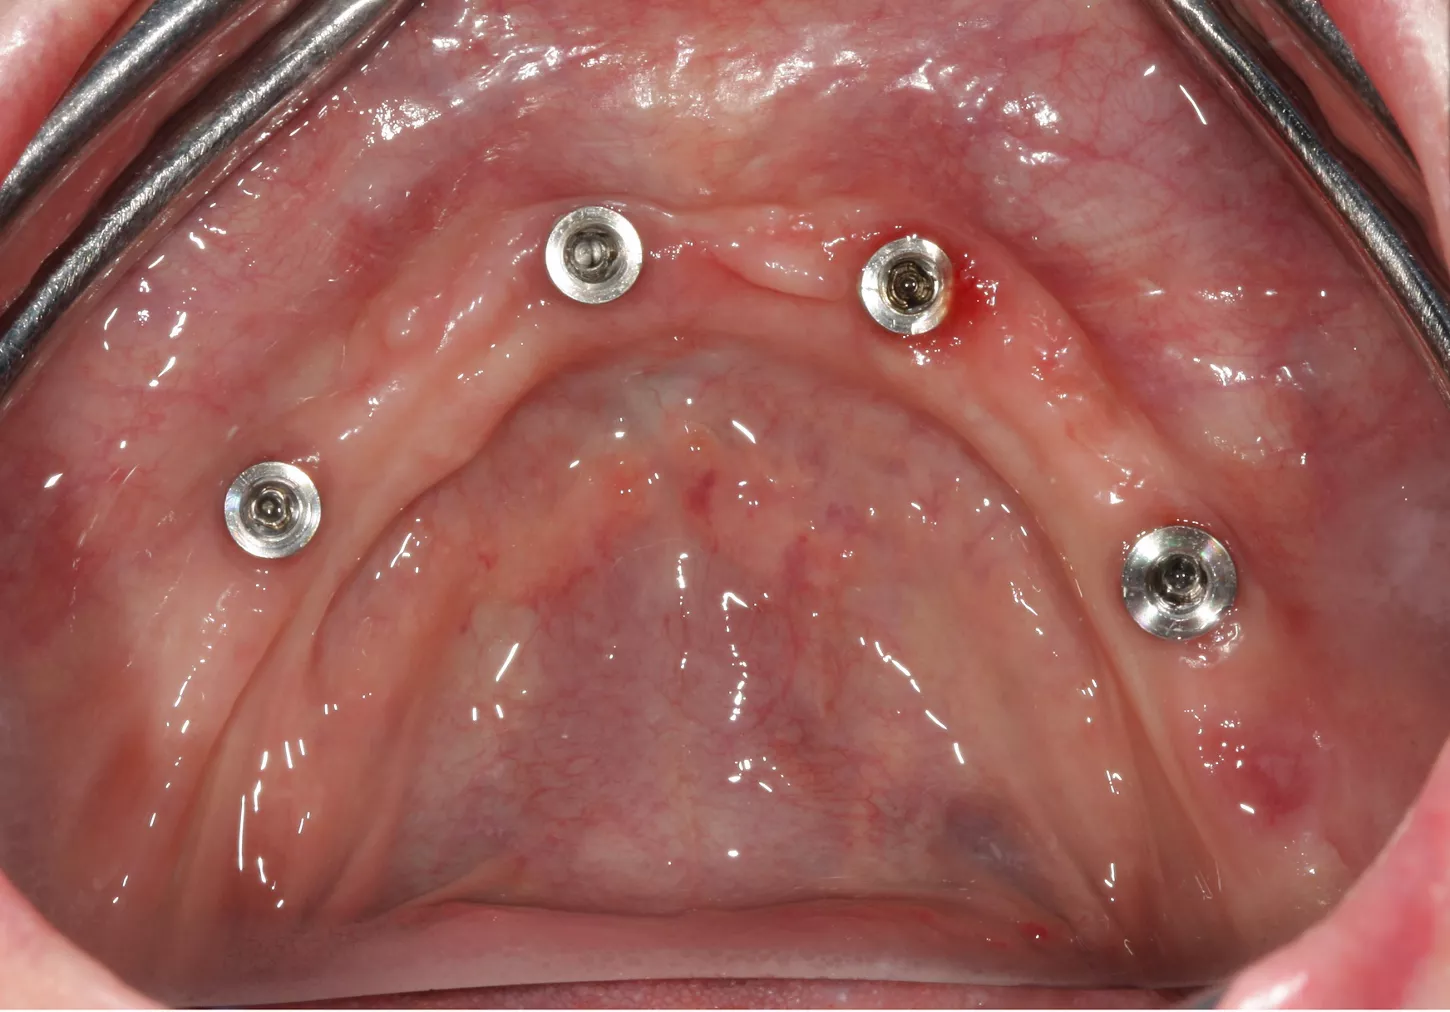

13. Occlusal pictures of healing around the implants at 3 months follow-up upon removal of the provisional prosthesis.